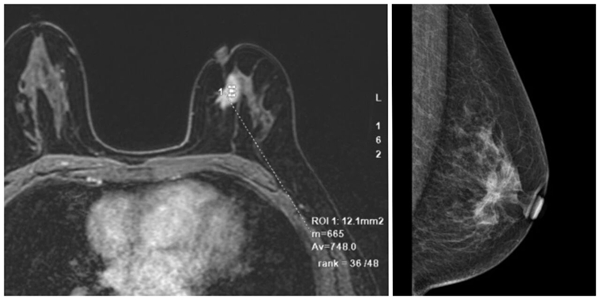

兩個月前,患者劉女士(化名)無意間摸到右乳有一個“鴿子蛋”大小的“疙瘩”。由于“疙瘩”不疼不癢,她起初并未在意。直到兒女偶然得知此事并反復(fù)勸說,劉女士才意識到問題的嚴(yán)重性,經(jīng)多方打聽,她慕名來到青島市婦女兒童醫(yī)院,找到了張堅(jiān)教授。作為從事乳腺甲狀腺、普外科專業(yè)近 30 年的資深專家,張堅(jiān)教授在乳腺腫瘤、甲狀腺腫瘤的微創(chuàng)手術(shù)及綜合治療方面有著深厚的造詣,尤其在保乳手術(shù)、乳腺腫瘤整形手術(shù)(OPS)領(lǐng)域積累了豐富的臨床經(jīng)驗(yàn)。面對劉女士的情況,張堅(jiān)教授首先進(jìn)行了初步觸診,憑借敏銳的專業(yè)判斷,他意識到這個“鴿子蛋”腫物性質(zhì)不容樂觀。隨后,結(jié)合超聲、鉬靶、核磁共振、穿刺活檢等多項(xiàng)檢查結(jié)果,張堅(jiān)教授明確診斷劉女士所患疾病為中央?yún)^(qū)乳腺癌—— 一種發(fā)生在乳頭乳暈區(qū)周圍的特殊位置乳腺癌。

面對患者的焦慮與期待,張堅(jiān)教授用專業(yè)的解讀為她注入了信心。他耐心解釋,隨著醫(yī)學(xué)技術(shù)的發(fā)展,中央?yún)^(qū)腫瘤已不再是保乳手術(shù)的絕對禁忌,只要經(jīng)過科學(xué)評估與精準(zhǔn)操作,中央?yún)^(qū)乳腺癌患者同樣可以實(shí)現(xiàn)保乳治療。不過,張堅(jiān)教授也客觀指出,傳統(tǒng)的中央?yún)^(qū)乳腺癌保乳手術(shù)存在明顯局限 —— 將病變所在乳腺組織切除后直接縫合切口,會讓乳房失去圓潤外觀,還會破壞雙側(cè)乳房的對稱性。張堅(jiān)教授并未局限于傳統(tǒng)術(shù)式。他查閱了大量國內(nèi)外最新文獻(xiàn)資料,結(jié)合國際前沿診療指南,從腫瘤切除范圍到術(shù)后修復(fù)整形方案,結(jié)合該病人乳頭到下皺襞距離較短、乳房橫徑較寬的特點(diǎn),逐一分析論證不同方案的優(yōu)缺點(diǎn)。在與患者及家屬進(jìn)行充分溝通,詳細(xì)解釋手術(shù)原理、風(fēng)險及預(yù)期效果后,最終確定了右側(cè)乳腺癌保乳根治術(shù)+前哨淋巴結(jié)活檢術(shù)+腫瘤整形手術(shù) (改良Grisotti推進(jìn)旋轉(zhuǎn)皮瓣技術(shù)) 的個性化治療方案。

1. 綜合解讀乳腺超聲、鉬靶、增強(qiáng)MRI、甲狀腺超聲等影像學(xué)報告,結(jié)合術(shù)前穿刺病理、術(shù)后分子病理、基因檢測等手段,為乳甲結(jié)節(jié)或腫瘤患者,提供一站式的最優(yōu)化決策方案。